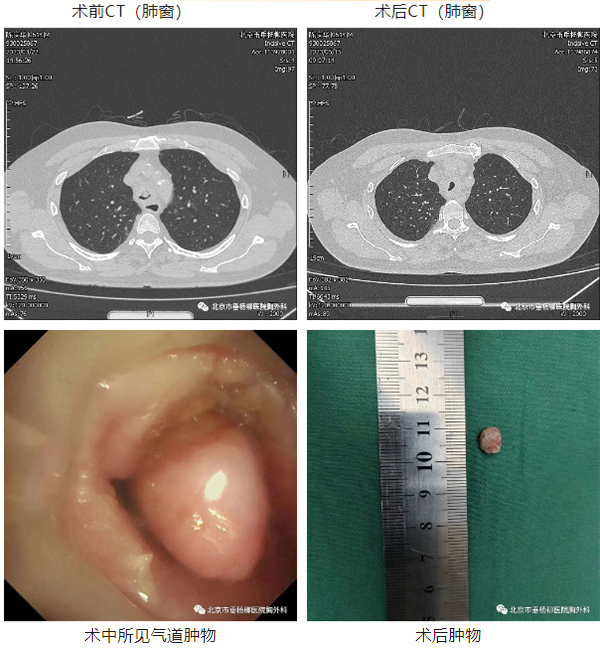

患者男性,61岁,主因“发现气管息肉1年余,喘息1月余。”,以“气管肿物”入院,胸部CT:气管造瘘口下方可见类圆形实性肿物,约占气管横径3/4,最长直径约13mm,边界较清晰。术中支气管镜下可见表面光滑、蒂窄的类圆形息肉样组织。手术历时40分钟,使用氩气刀局部灼烧基底部组织并止血,使用圈套器完整切除肿物,后使用低温冷冻消融局部清理基底部近气管组织,术后病理回示:中-重度非典型增生,术后患者恢复良好,喘息等呼吸道症状明显缓解,术后3天出院。